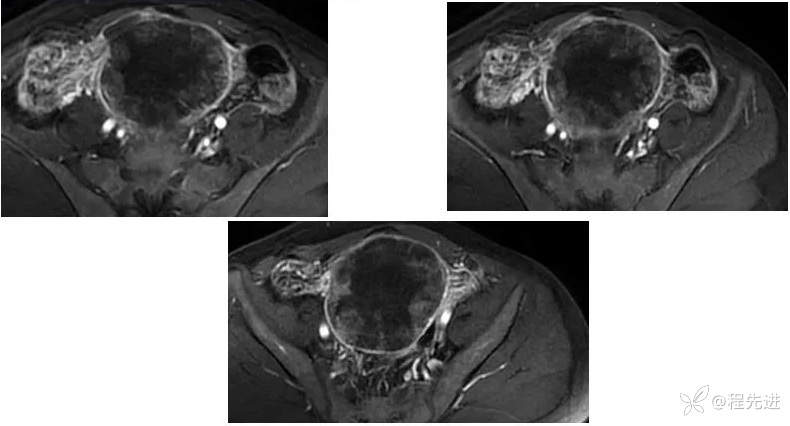

【腹盆】特别精彩病例|下腹痛20余天,男性病人腹腔巨大肿块该如何诊断

【患者信息】:男,41岁

【主诉】:下腹痛20余天

既往史:隐睾

肿瘤标志物:甲胎蛋白(AFP)>10000

增强: